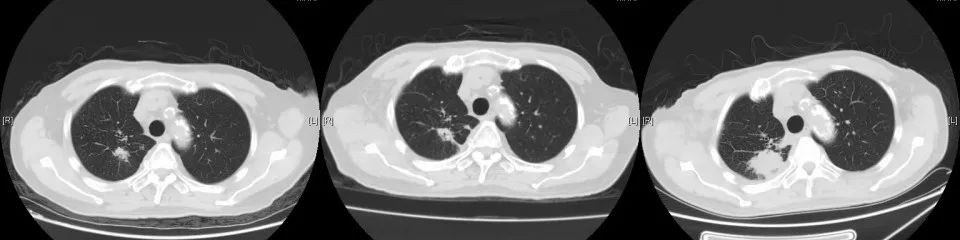

2017年7月行全身PET-CT提示右肺上叶高代谢病灶。2017年8月份行肺穿刺活检未能明确病理诊断。2017年10月份再次行全身PET-CT:右上肺结节增大,代谢增高,与家属商量后,外院予试用口服“吉非替尼”靶向治疗。

2018年1月复查胸部CT:右肺占位较前增大,余无明显特殊不适。外院再次行肺穿刺活检,病理:右肺组织见癌转移(符合膀胱癌肺转移)。2018年3月14-29日于我院行肺转移灶局部放疗。2018年5月15日-7月11日予标准方案化疗2周期。期间病情稳定。2018年10月复查,局部肺转移灶增大进展、且出现肺新转移灶,评估疗效PD,行NGS全基因检测,根据检测结果,即选用阿法替尼口服行靶向治疗。

CT变化: